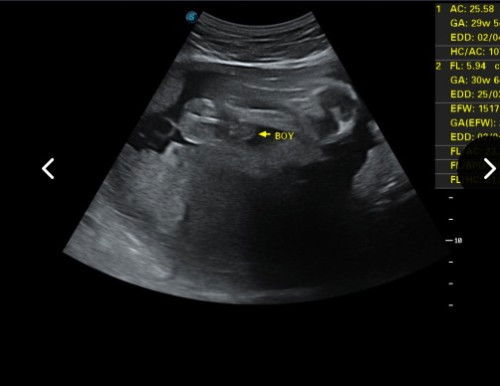

Sy da 6kali scan d klinik yg brbeza dan doktor yg brbeza kptusan jantina juga brbeza2 stiap pndgan doktor..sbnrnya sy dan husbnd tak kisah pun psl jantina ne..cuma kita excited ja ..#firstmom scan 27 weeks doktor kata baby girl,last scan d klinik lain 30weeks doktor tu kata baby boys..yg ne gmbr sy srtakan..betul2 da ka pistol ne..